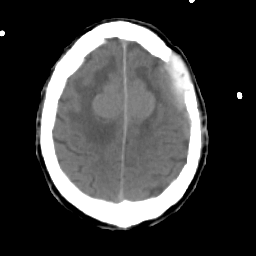

Meningioma: Roentgen-ray CT #2 -- Slice #16

[Home][Help][Clinical] Slice 16